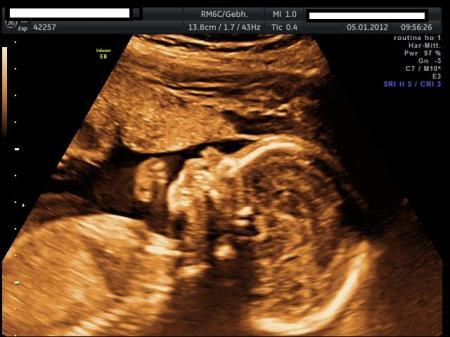

und noch das Seitenprofil...man sieht die Fingerchen voll gut.

Total niedlich sieht sie aus. Schönres Profil. Wenn wir alle soweit sind, wie auf dein 2. Bild, dann sind wir glücklich. Man kann es kaum erwarten. Noch eine schöne restliche Kugelzeit. Lg